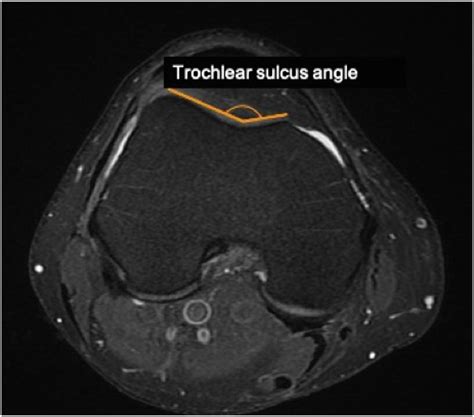

The patella is designed to glide vertically within the femoral groove (the trochlear groove) of the femur. When the mechanics of the knee are balanced, this movement is seamless. However, lateral patellar tilt happens when the soft tissues—specifically the lateral retinaculum on the outside of the knee—become too tight, while the muscles on the inside are relatively weak. This imbalance causes the kneecap to tip outward, increasing pressure on the lateral facet of the patella. Over time, this abnormal tracking can lead to cartilage wear, inflammation, and chronic pain, a condition often categorized under patellofemoral pain syndrome (PFPS).

• Anatomical Factors: Some individuals are born with a shallower femoral groove, making the kneecap more susceptible to drifting out of alignment.

• lateral patellar tilt angle